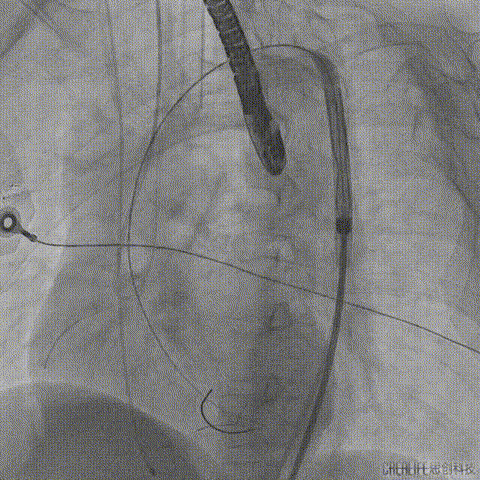

术前CT分析右侧的冠脉风险较高,球囊预扩前右冠开口处预放一个冠脉保护支架,采用18mm球囊预扩,有轻微腰征,无造影剂渗漏;

右侧冠脉保护准备

球囊预扩

TaurusElite输送系统轻松过弓、跨瓣,AV23瓣膜瓣环上约2mm释放;

TaurusElite轻松过弓

瓣膜释放